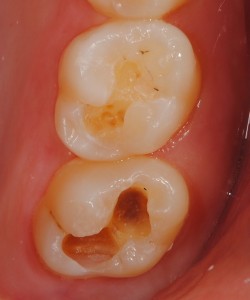

症例②